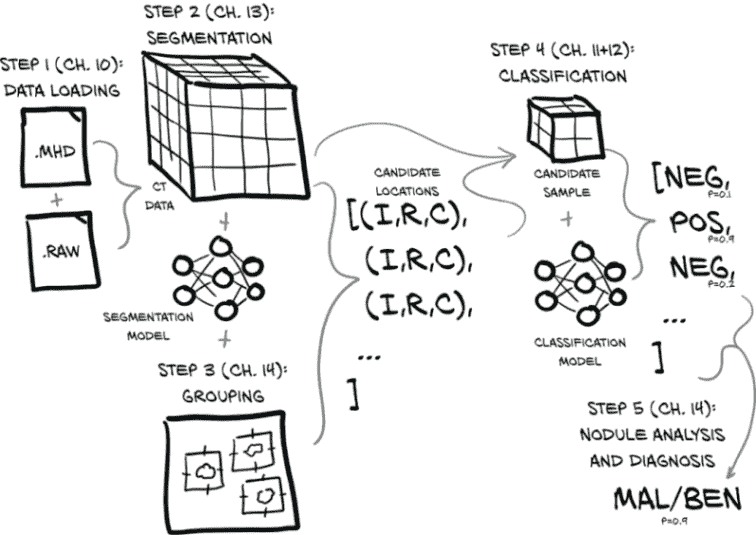

现在我们已经掌握了 CT 扫描的基础知识,让我们讨论一下我们项目的结构。大部分磁盘上的字节将用于存储包含密度信息的 CT 扫描的 3D 数组,我们的模型将主要消耗这些 3D 数组的各种子切片。我们将使用五个主要步骤,从检查整个胸部 CT 扫描到给患者做出肺癌诊断。

我们在图 9.4 中展示的完整端到端解决方案将加载 CT 数据文件以生成包含完整 3D 扫描的Ct实例,将其与执行分割(标记感兴趣的体素)的模块结合,然后将有趣的体素分组成小块,以寻找候选结节。

图 9.4 完整胸部 CT 扫描并确定患者是否患有恶性肿瘤的端到端过程

结节位置与 CT 体素数据结合,产生结节候选,然后可以由我们的结节分类模型检查它们是否实际上是结节,最终是否是恶性的。后一项任务特别困难,因为恶性可能仅从 CT 成像中无法明显看出,但我们将看看我们能走多远。最后,每个单独的结节分类可以组合成整体患者诊断。

更详细地说,我们将执行以下操作:

将我们的原始 CT 扫描数据加载到一个可以与 PyTorch 一起使用的形式中。将原始数据放入 PyTorch 可用的形式将是您面临的任何项目的第一步。对于 2D 图像数据,这个过程稍微复杂一些,对于非图像数据则更简单。

使用 PyTorch 识别肺部潜在肿瘤的体素,实现一种称为分割的技术。这大致相当于生成应该输入到我们第 3 步分类器中的区域的热图。这将使我们能够专注于肺部内部的潜在肿瘤,并忽略大片无趣的解剖结构(例如,一个人不能在胃部患肺癌)。

将有趣的体素分组成块:也就是候选结节(有关结节的更多信息,请参见图 9.5)。在这里,我们将找到热图上每个热点的粗略中心。

使用 3D 卷积将候选结节分类为实际结节或非结节。

使用组合的每个结节分类来诊断患者。

图 9.4 仅描述了在构建和训练所有必要模型后通过系统的最终路径。训练相关模型所需的实际工作将在我们接近实施每个步骤时详细说明。

我们将用于训练的数据为步骤 3 和 4 提供了人工注释的输出。这使我们可以将步骤 2 和 3(识别体素并将其分组为结节候选)几乎视为与步骤 4(结节候选分类)分开的项目。人类专家已经用结节位置注释了数据,因此我们可以按照自己喜欢的顺序处理步骤 2 和 3 或步骤 4。

我们将首先处理步骤 1(数据加载),然后跳到步骤 4,然后再回来实现步骤 2 和 3,因为步骤 4(分类)需要一种类似于我们在第八章中使用的方法,即使用多个卷积和池化层来聚合空间信息,然后将其馈送到线性分类器中。一旦我们掌握了分类模型,我们就可以开始处理步骤 2(分割)。由于分割是更复杂的主题,我们希望在不必同时学习分割和 CT 扫描以及恶性肿瘤的基础知识的情况下解决它。相反,我们将在处理一个更熟悉的分类问题的同时探索癌症检测领域。

我们将在第十章中进行第 1 步数据加载工作,第十一章和第十二章将专注于解决分类这些结节的问题。之后,我们将回到第十三章工作于第 2 步(使用分割找到候选肿瘤),然后我们将在第十四章中结束本书的第 2 部分,通过实现第 3 步(分组)和第 5 步(结节分析和诊断)的端到端项目。

让我们在图 9.7 中重复我们的高层概述。

图 9.7 完成全胸 CT 扫描并确定患者是否患有恶性肿瘤的端到端过程